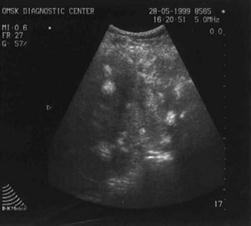

Ультрасонограмма щитовидной железы

Очень информативным является исследование УЗИ щитовидной железы (рис.1). Оптимальными для исследования ЩЖ служат датчики с частотой 7,5 и 10 МГц. На что нужно обращать внимание: гипоэхогенность, наличие микрокальцинатов (макрокальцинаты свидетельствуют скорее не о злокачественном характере узла, а о длительности существования крупного узла), отсутствие по периферии ограничительного ободка, гипо - и аваскулярность очаговых изменений, дорзальное ослабление сигнала, солитарность, локализация узла в перешейке. Наиболее достоверными признаками злокачественности, из выше перечисленных, является гипоэхогенность узла и наличие в нем микрокальцината (данные признаки характерны для папиллярного рака).

УЗИ является достаточно чувствительным методом, однако с его помощью не представляется возможным определить, является ли узел злокачественной опухолью или нет. Заключение УЗИ должно носить описательный характер и не содержать клинического диагноза.